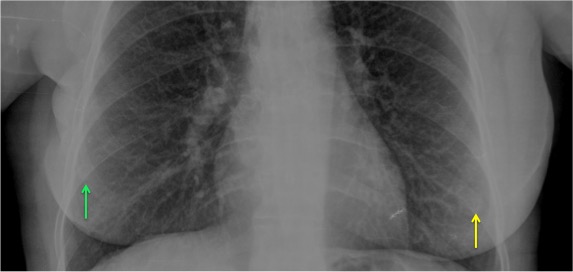

CASO: Operada de cáncer de mama izquierda en revisión.

Hallazgos:

- Prótesis mamaria izquierda (obsevar el aumento de densidad homogéneo y de bordes bien definidos en la placa PA y lateral)

- Parénquimas pulmonares y silueta cardiomediastínica sin alteraciones significativas.